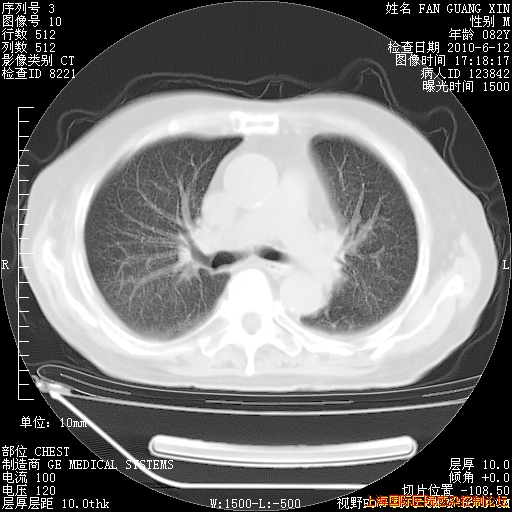

今天复查CT

今天CT

整整相隔30天的肺部CT好像有所好转啊。甲强龙减量第3天,需要观察体温。

海管,自昨日你和我通完话后,不知您岳父消化道症状有无缓解?体温怎样?阅读7.12日胸部ct,个人认为目前激素治疗是有效的,甲强龙减量是适宜的。因在抗痨治疗,需密切观察肝功、肾功能和血常规。不过,老年、长期住院和大量使用激素,很担心菌群失调发生